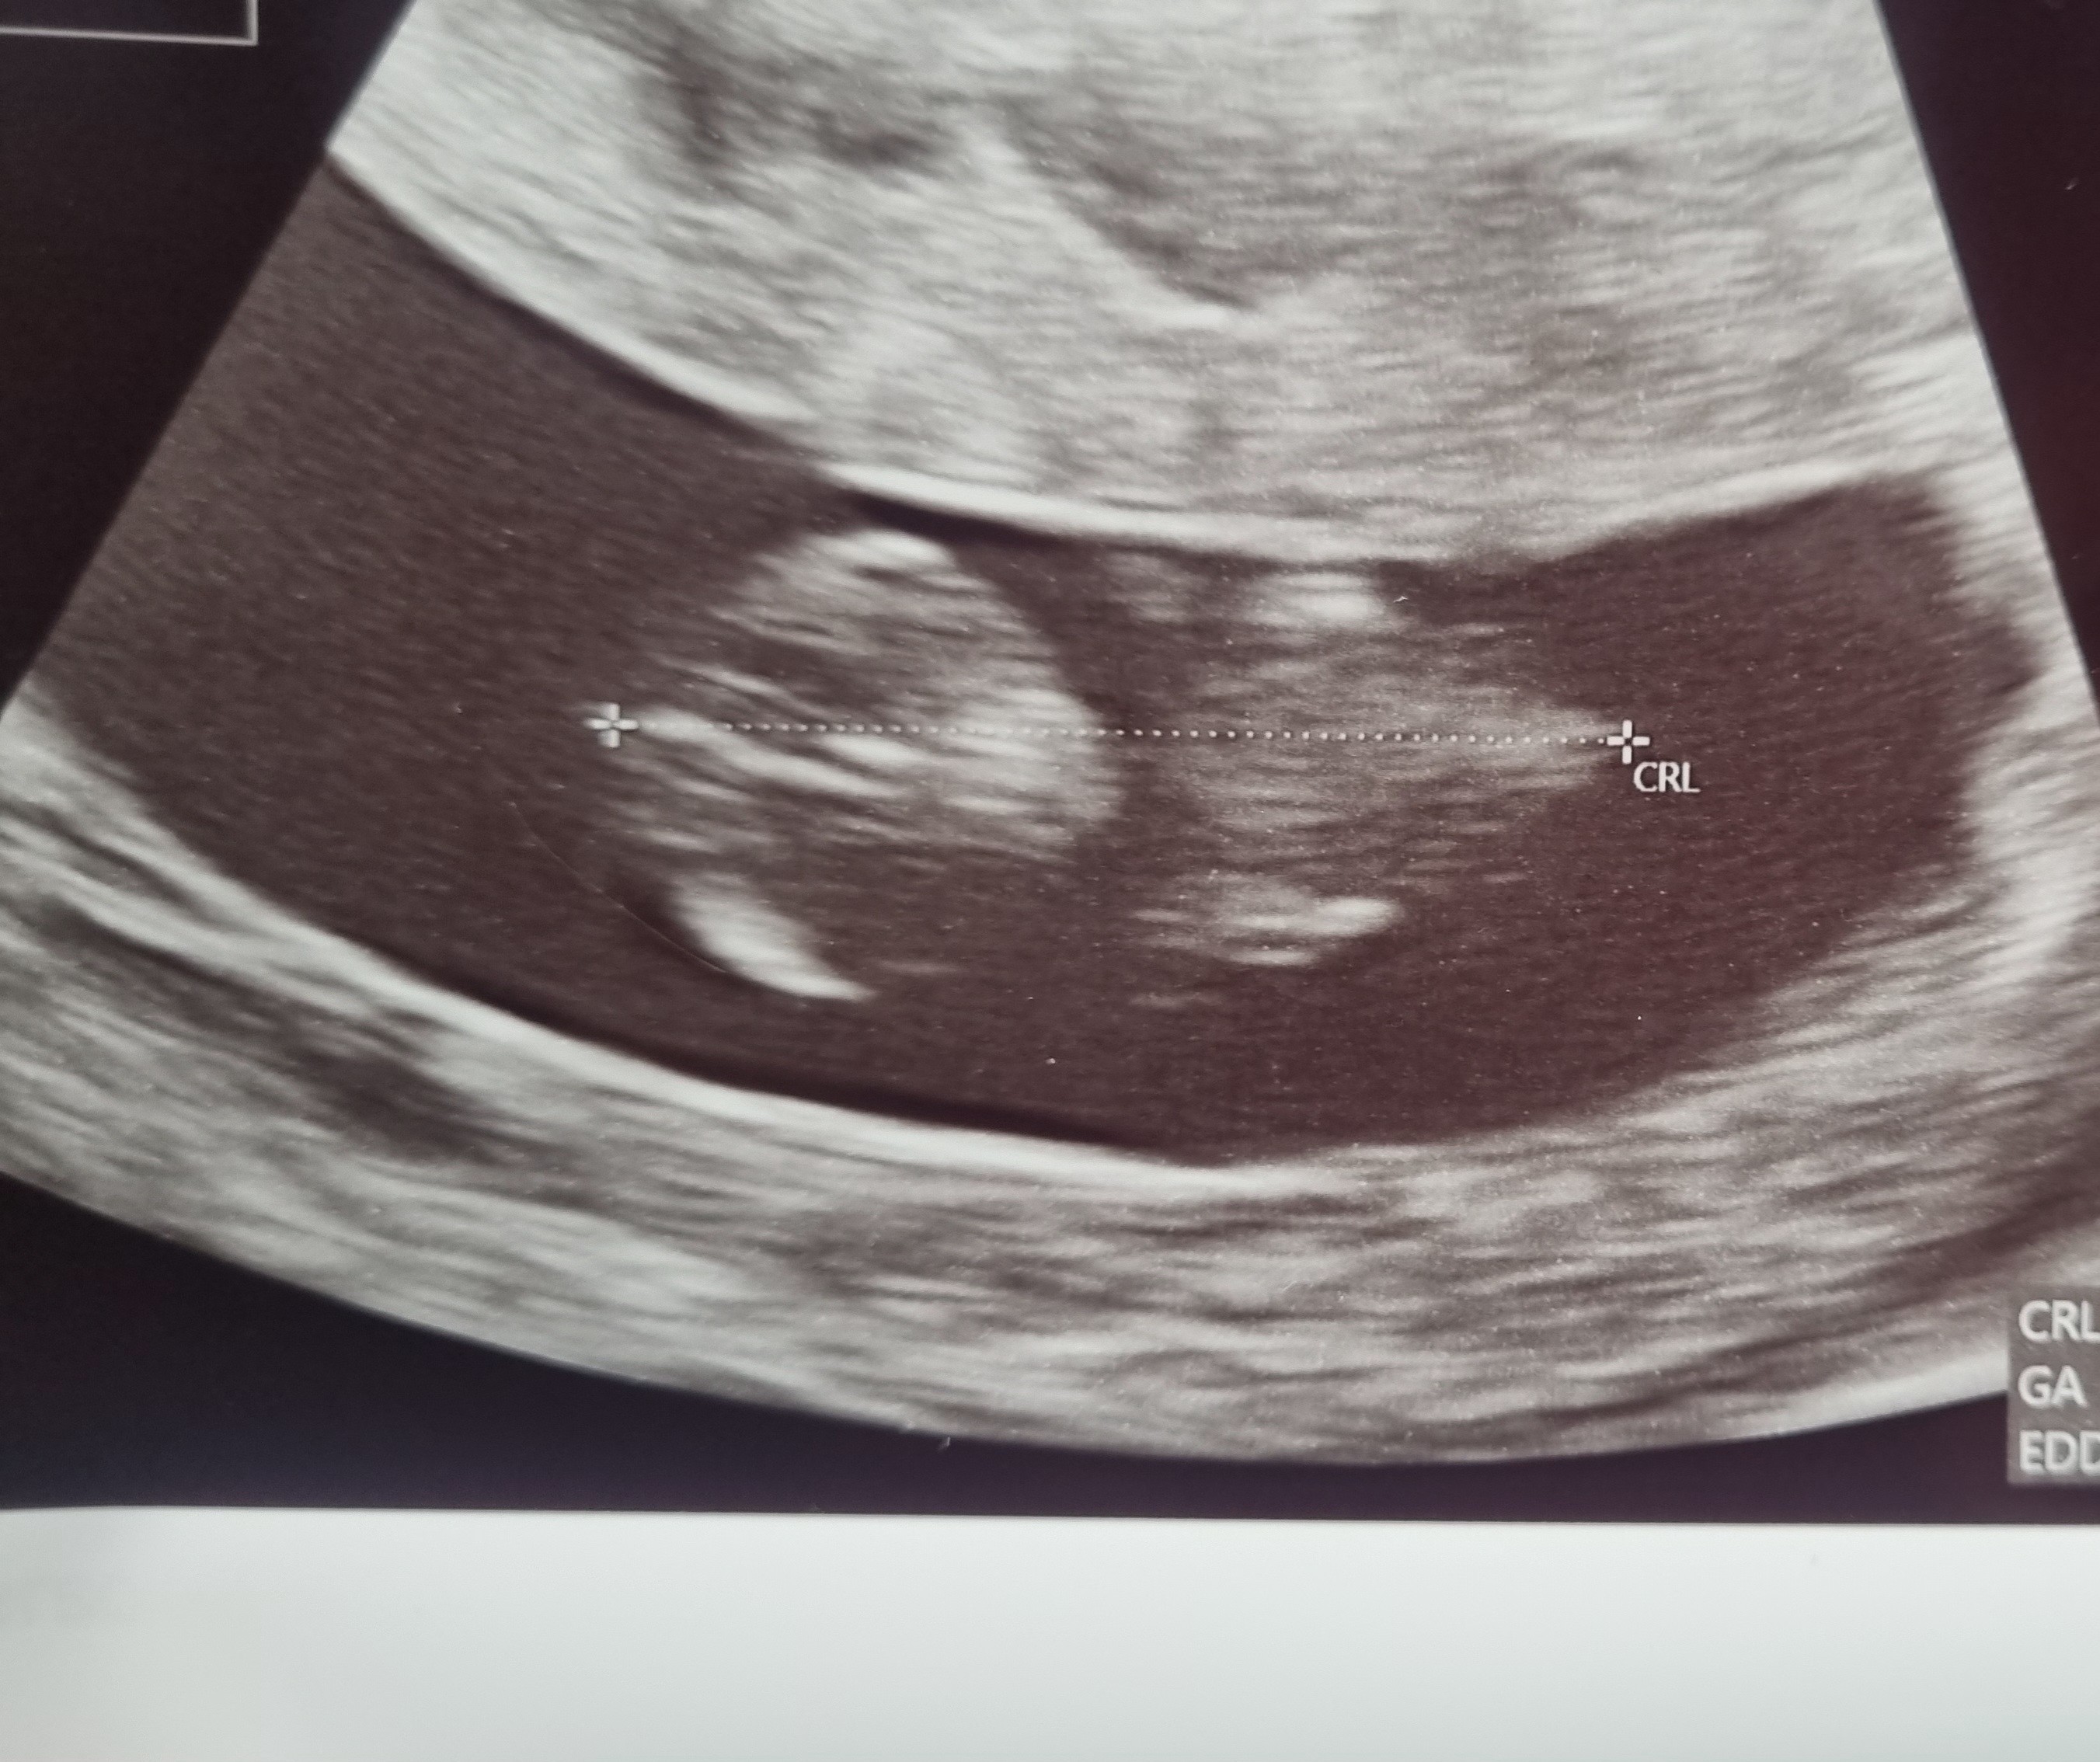

Jestem dziewczyny! Maleństwo żyje i ma się dobrze, ma aktualnie 1,45cm. 🥰 Serduszko bije już prawidłowo. Krwiak się jeszcze do końca nie wchłonął ale już jest mniejszy. Mi za to doszły leki na nadciśnienie bo do tej pory nie brałam (od kilku lat) a dziś moje ciśnienie wynosiło 160/100 i tętno 120 co jest u mnie dobrym wynikiem ale niekoniecznie bezpiecznym w ciąży... Także póki co dalej jakoś ciągniemy. 😊